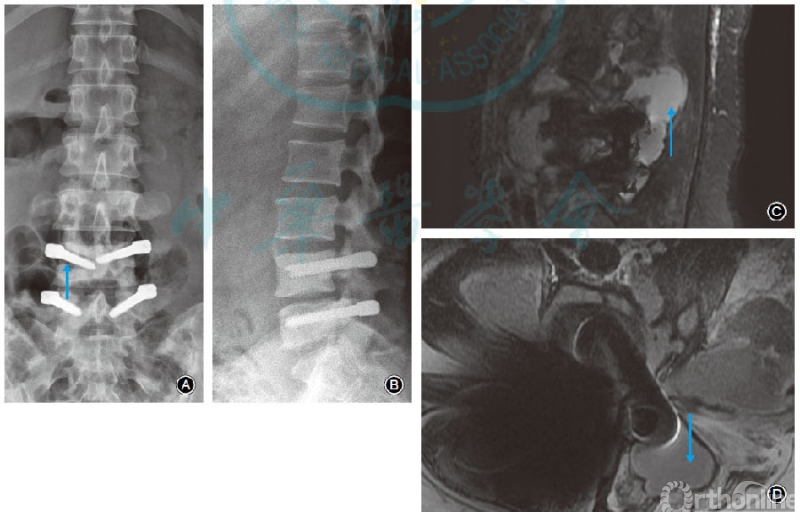

X线表现为螺钉周围骨质吸收、内固定松动11例。MRI表现为椎弓根螺钉周围积液者23例、椎旁积脓及腰大肌脓肿者1例(图1)。

图1 女,40岁,腰痛伴左下肢疼痛4d。3年前行L4-5椎间盘髓核摘除及Dynesys动态内固定,有糖尿病病史。白细胞计数为18.88×109/L,中性粒细胞比例0.91,C反应蛋白170.00mg/L,降钙素原0.35ng/ml,红细胞沉降率120.00mm/1h。诊断为腰椎内固定术后晚期感染,予以内固定取出。A腰椎正位X线片示L4椎弓根螺钉周围骨质吸收、内固定松动(箭头所示);B腰椎侧位X线片示L4椎弓根螺钉周围骨质吸收、内固定松动,L4,5椎体骨质硬化;C腰椎MRI矢状面脂肪抑制像示椎旁积脓(箭头所示);D腰椎MRI横断面T2WI片示椎弓根螺钉及间隔器周围积脓伴双侧腰大肌脓肿(箭头所示)